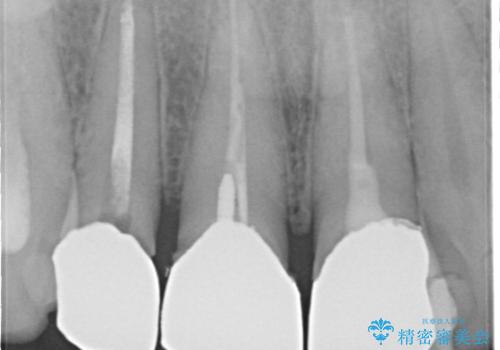

- 前歯のかぶせ物を自然な色味のものにしたいとのことで、来院されました。

保険適用のかぶせ物が装着されており、適合も悪く、変色している状態でした。

土台からの、再治療を行い、オールセラミッククラウンの装着を行う計画としました。